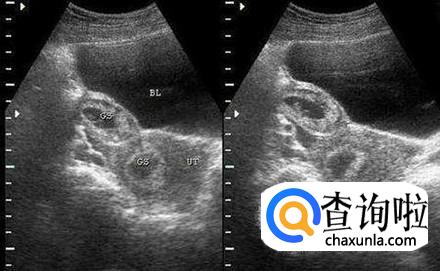

要想了解恶性葡萄胎是什么的话,我们就需要先对葡萄胎有一定的了解,葡萄胎是女性在妊娠之后由于间质高度水肿等情况所形成的相连串状水泡,也被称之为是水泡状胎块。

恶性葡萄胎是葡萄胎在进行恶变之后或者是绒毛膜发生了癌变之后所形成的,一般来说多数在清楚葡萄胎6个月时间之内发生,发病率在5%-20%之间,病症特点就是绒毛会随着血循环脱落转移。